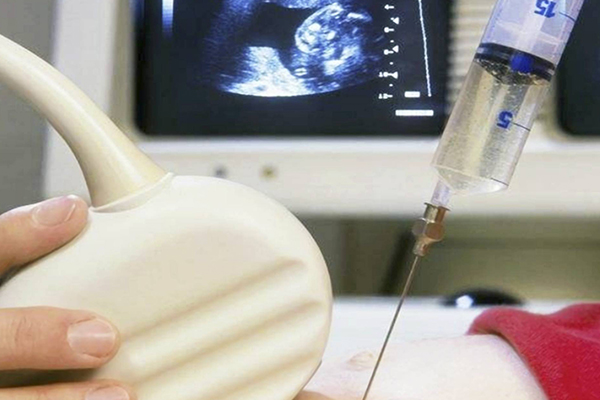

12周做nt检查时,nt值在正常范围内,什么问题都没有。想提醒孕妈,如果nt值正常,那么孩子基本上不会有太大的问题,但是如果为了安全,可以做详细的排查。因为直接做羊水穿刺,没有做唐筛检查,就等着羊穿,今年因为赶上了疫情,所以羊穿推迟了将近三周。做羊穿的过程很顺利,什么问题都没有。麻烦的就是等待时间较长,半个月后羊穿出结果了,孩子的染色体核型没有问题,但是基因芯片却查出1号染色体缺失,4号染色体缺失1.16兆。

羊水穿刺可明确染色体异常情况